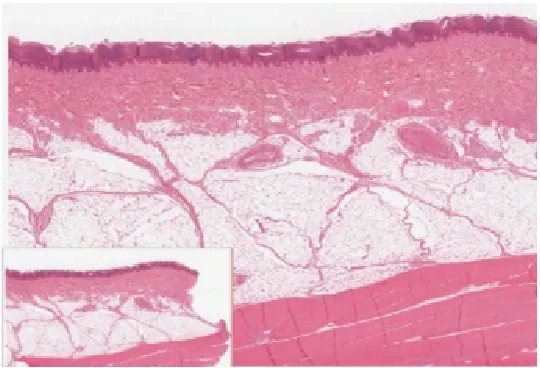

The Epidermis

The epidermis is composed of keratinized, stratified squamous epithelium. It is made of four or five layers of epithelial cells, depending on its location in the body. It does not have any blood vessels within it (i.e., it is avascular). Skin that has four layers of cells is referred to as “thin skin.” From deep to superficial, these layers are the stratum basale, stratum spinosum, stratum granulosum, and stratum corneum. Most of the skin can be classified as thin skin. “Thick skin” is found only on the palms of the hands and the soles of the feet. It has a fifth layer, called the stratum lucidum, located between the stratum corneum and the stratum granulosum (Figure 5.3).

Figure 5.3 Thin Skin versus Thick Skin These slides show cross-sections of the epidermis and dermis of (a) thin and (b) thick skin. Note the significant difference in the thickness of the epithelial layer of the thick skin. From top, LM × 40, LM × 40. (Micrographs provided by the Regents of University of Michigan Medical School © 2012)